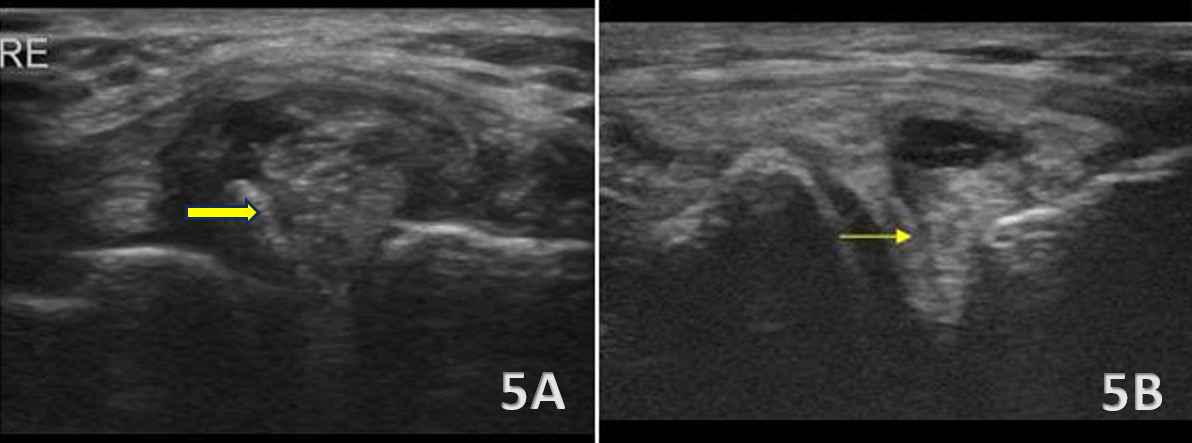

Lateral Meniscus Tear and Cyst Formation

Figures 5A and 5B: Tears of the lateral meniscus can be more subtle on ultrasound due to its deeper location and the presence of overlying structures such as the LCL and popliteus tendon. Pathology is suggested by hypoechoic defects, irregular margins, or distortion of the normally well-defined triangular meniscal wedge. Additional findings may include abnormal contact between the meniscus and popliteus tendon, small displaced fragments or loose bodies adjacent to the joint line, and parameniscal cyst formation, which is commonly associated with lateral meniscal tears. Joint line fluid may further accentuate the tear plane. The application of gentle varus or valgus stress during imaging can improve visualization by accentuating meniscal extrusion or revealing instability within torn segments.